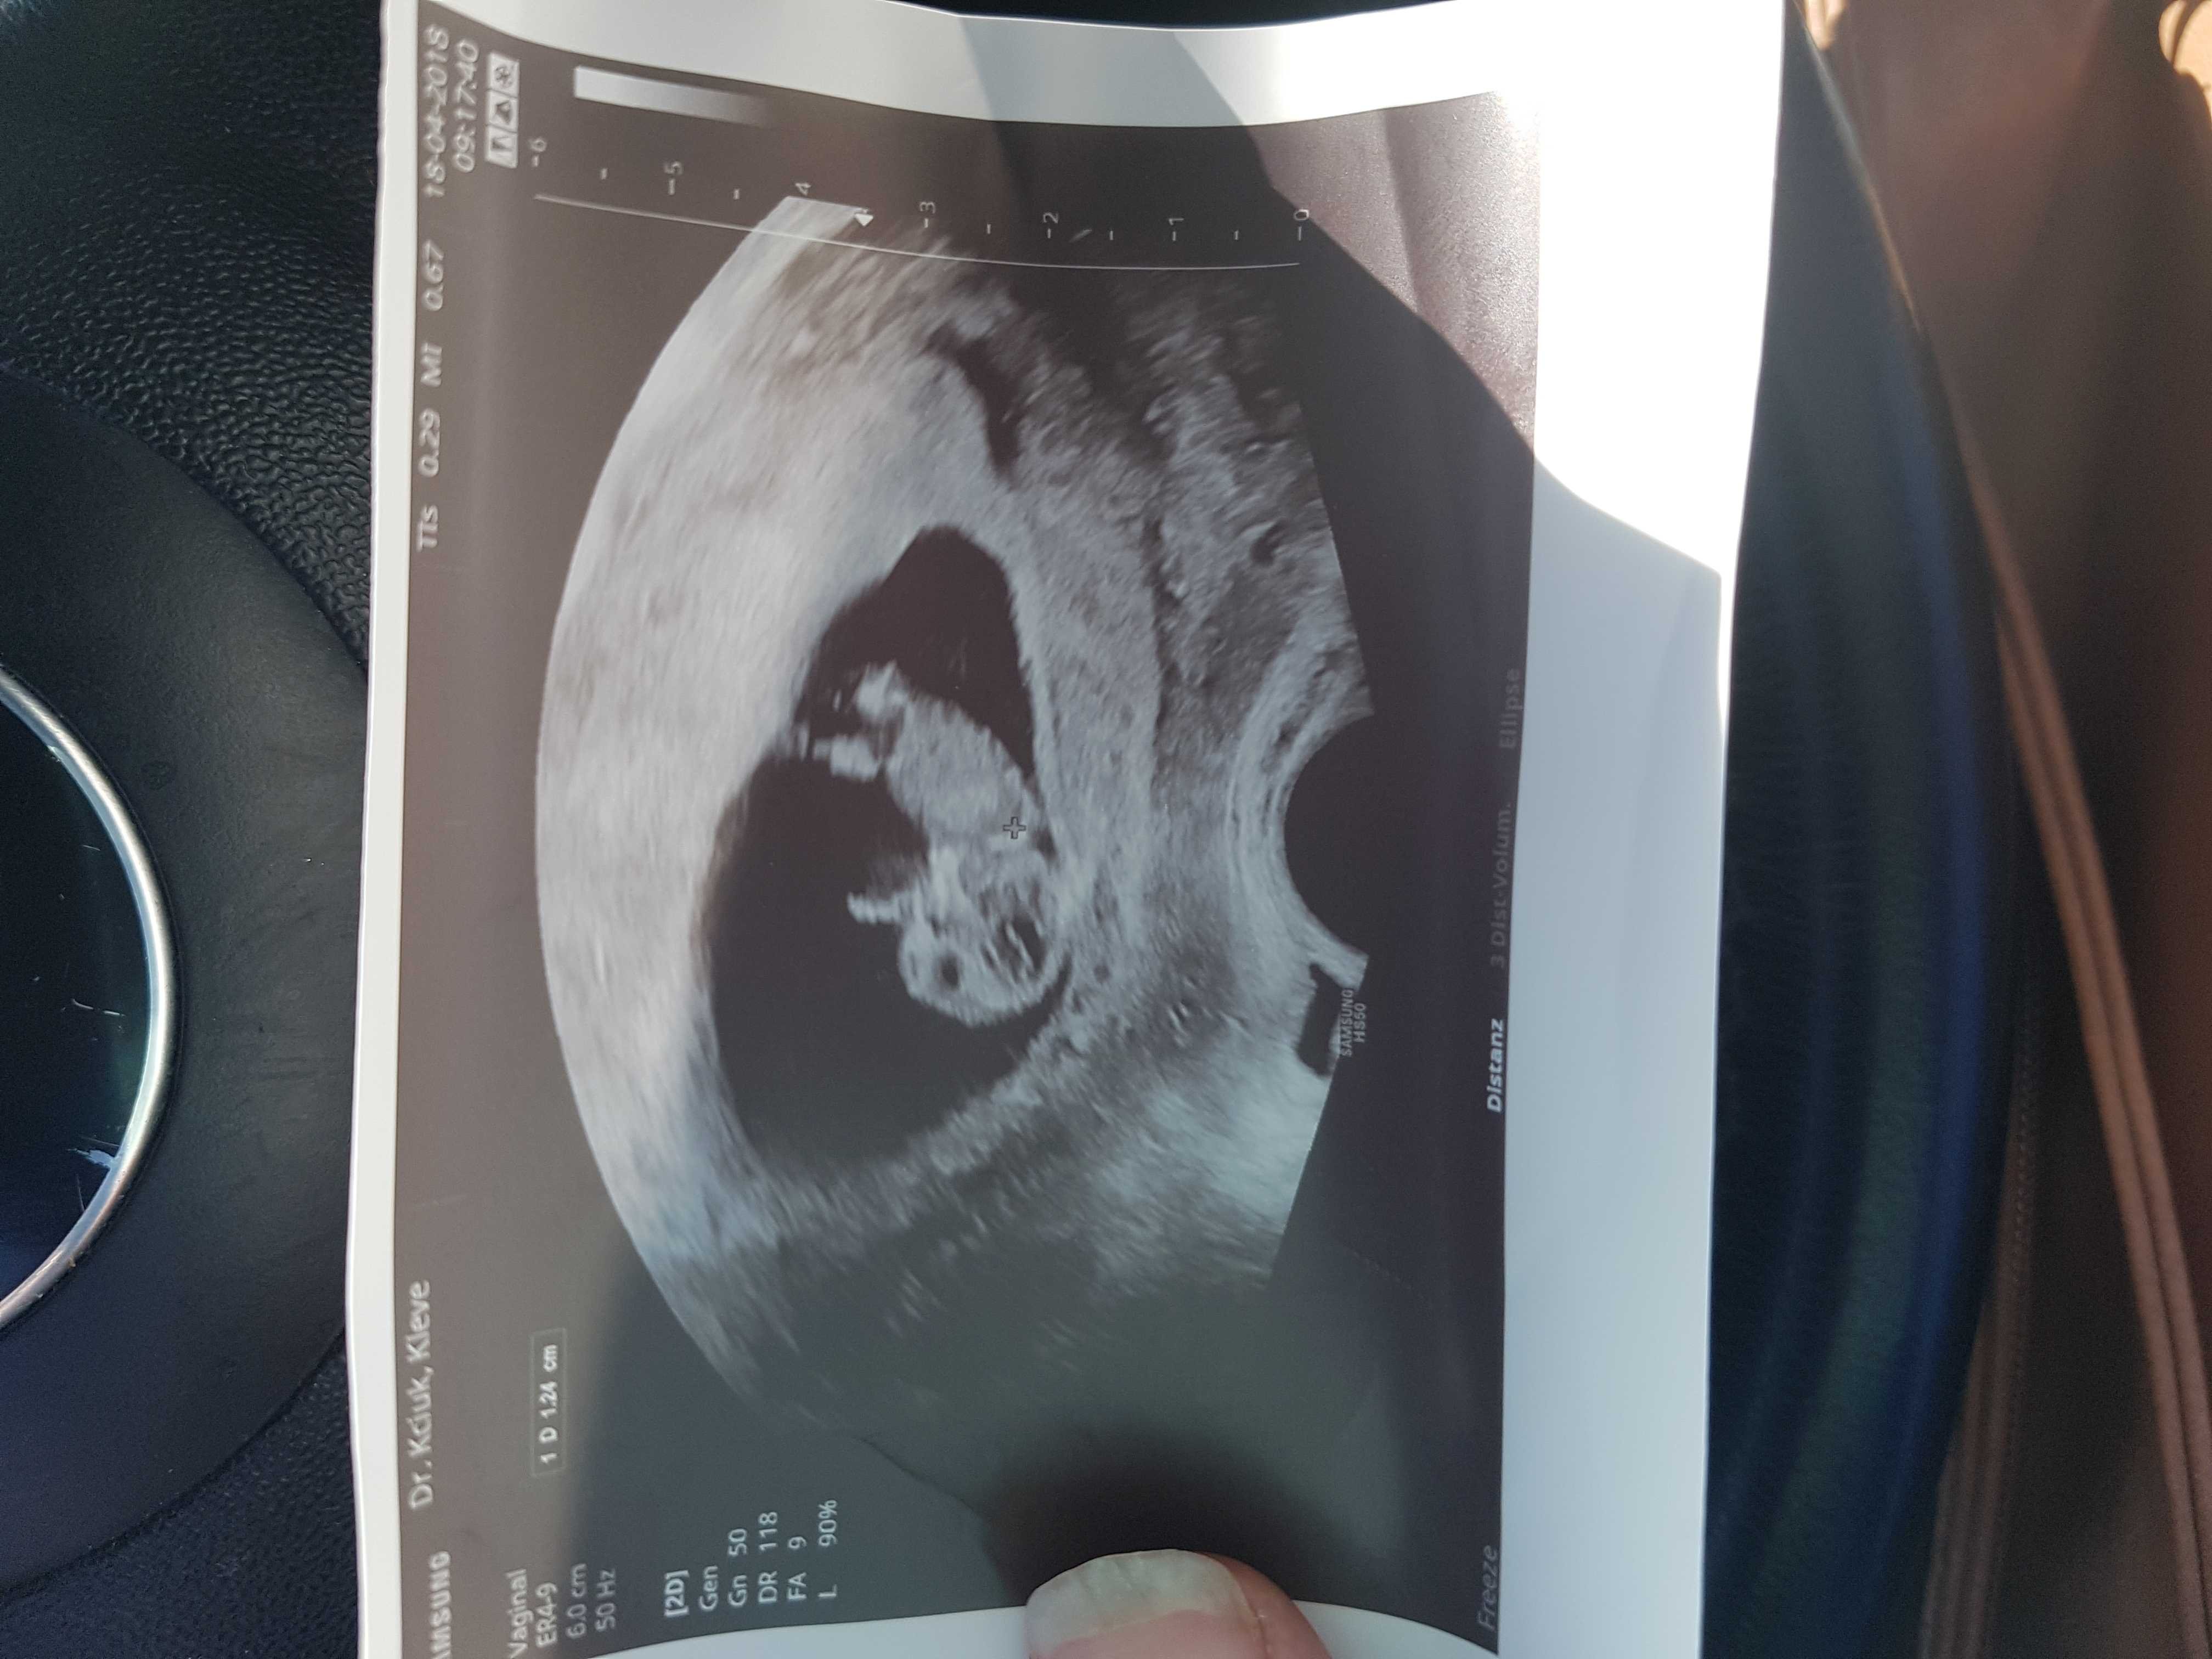

[emoji173][emoji173][emoji173][emoji173]A to moj maly czlowieczek 6 cm juz ma 10 +2Zobacz załącznik 847945

6 cm?! Duży człowiek!A to moj maly czlowieczek 6 cm juz ma 10 +2Zobacz załącznik 847945

Fajny ludzik. Mój ma 3cm i akurat w tygodniach 10+1A to moj maly czlowieczek 6 cm juz ma 10 +2Zobacz załącznik 847945

No ja mialam wczesniejsza owulacje tak okolo 10 dc pewnie dlatego jest wieksze od twojego albo bedzie mialo w przyszlosci 200 cm wzrostu [emoji4] [emoji4]Fajny ludzik. Mój ma 3cm i akurat w tygodniach 10+1

Szukalam w necie 11 tydzien 6- 8 cm to by sie zgadzalo jak wg wczesniejszej owulacji